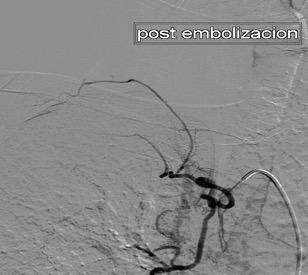

Paraganglioma

Aneurisma de arteria bronquial

3% segregan catecolaminas.

(En el área Paravertebral +/-50%.)

Intenso realce con el contraste.

32 años .Preeclampsia a los 19. Hipertensión no controlada. Masa paravertebral sólida que se realza intensamente con afectación ósea.

Yue Y t al. Asymptomatic left posterior mediastinal functional Paraganglioma. A case report. Medicine . 2019